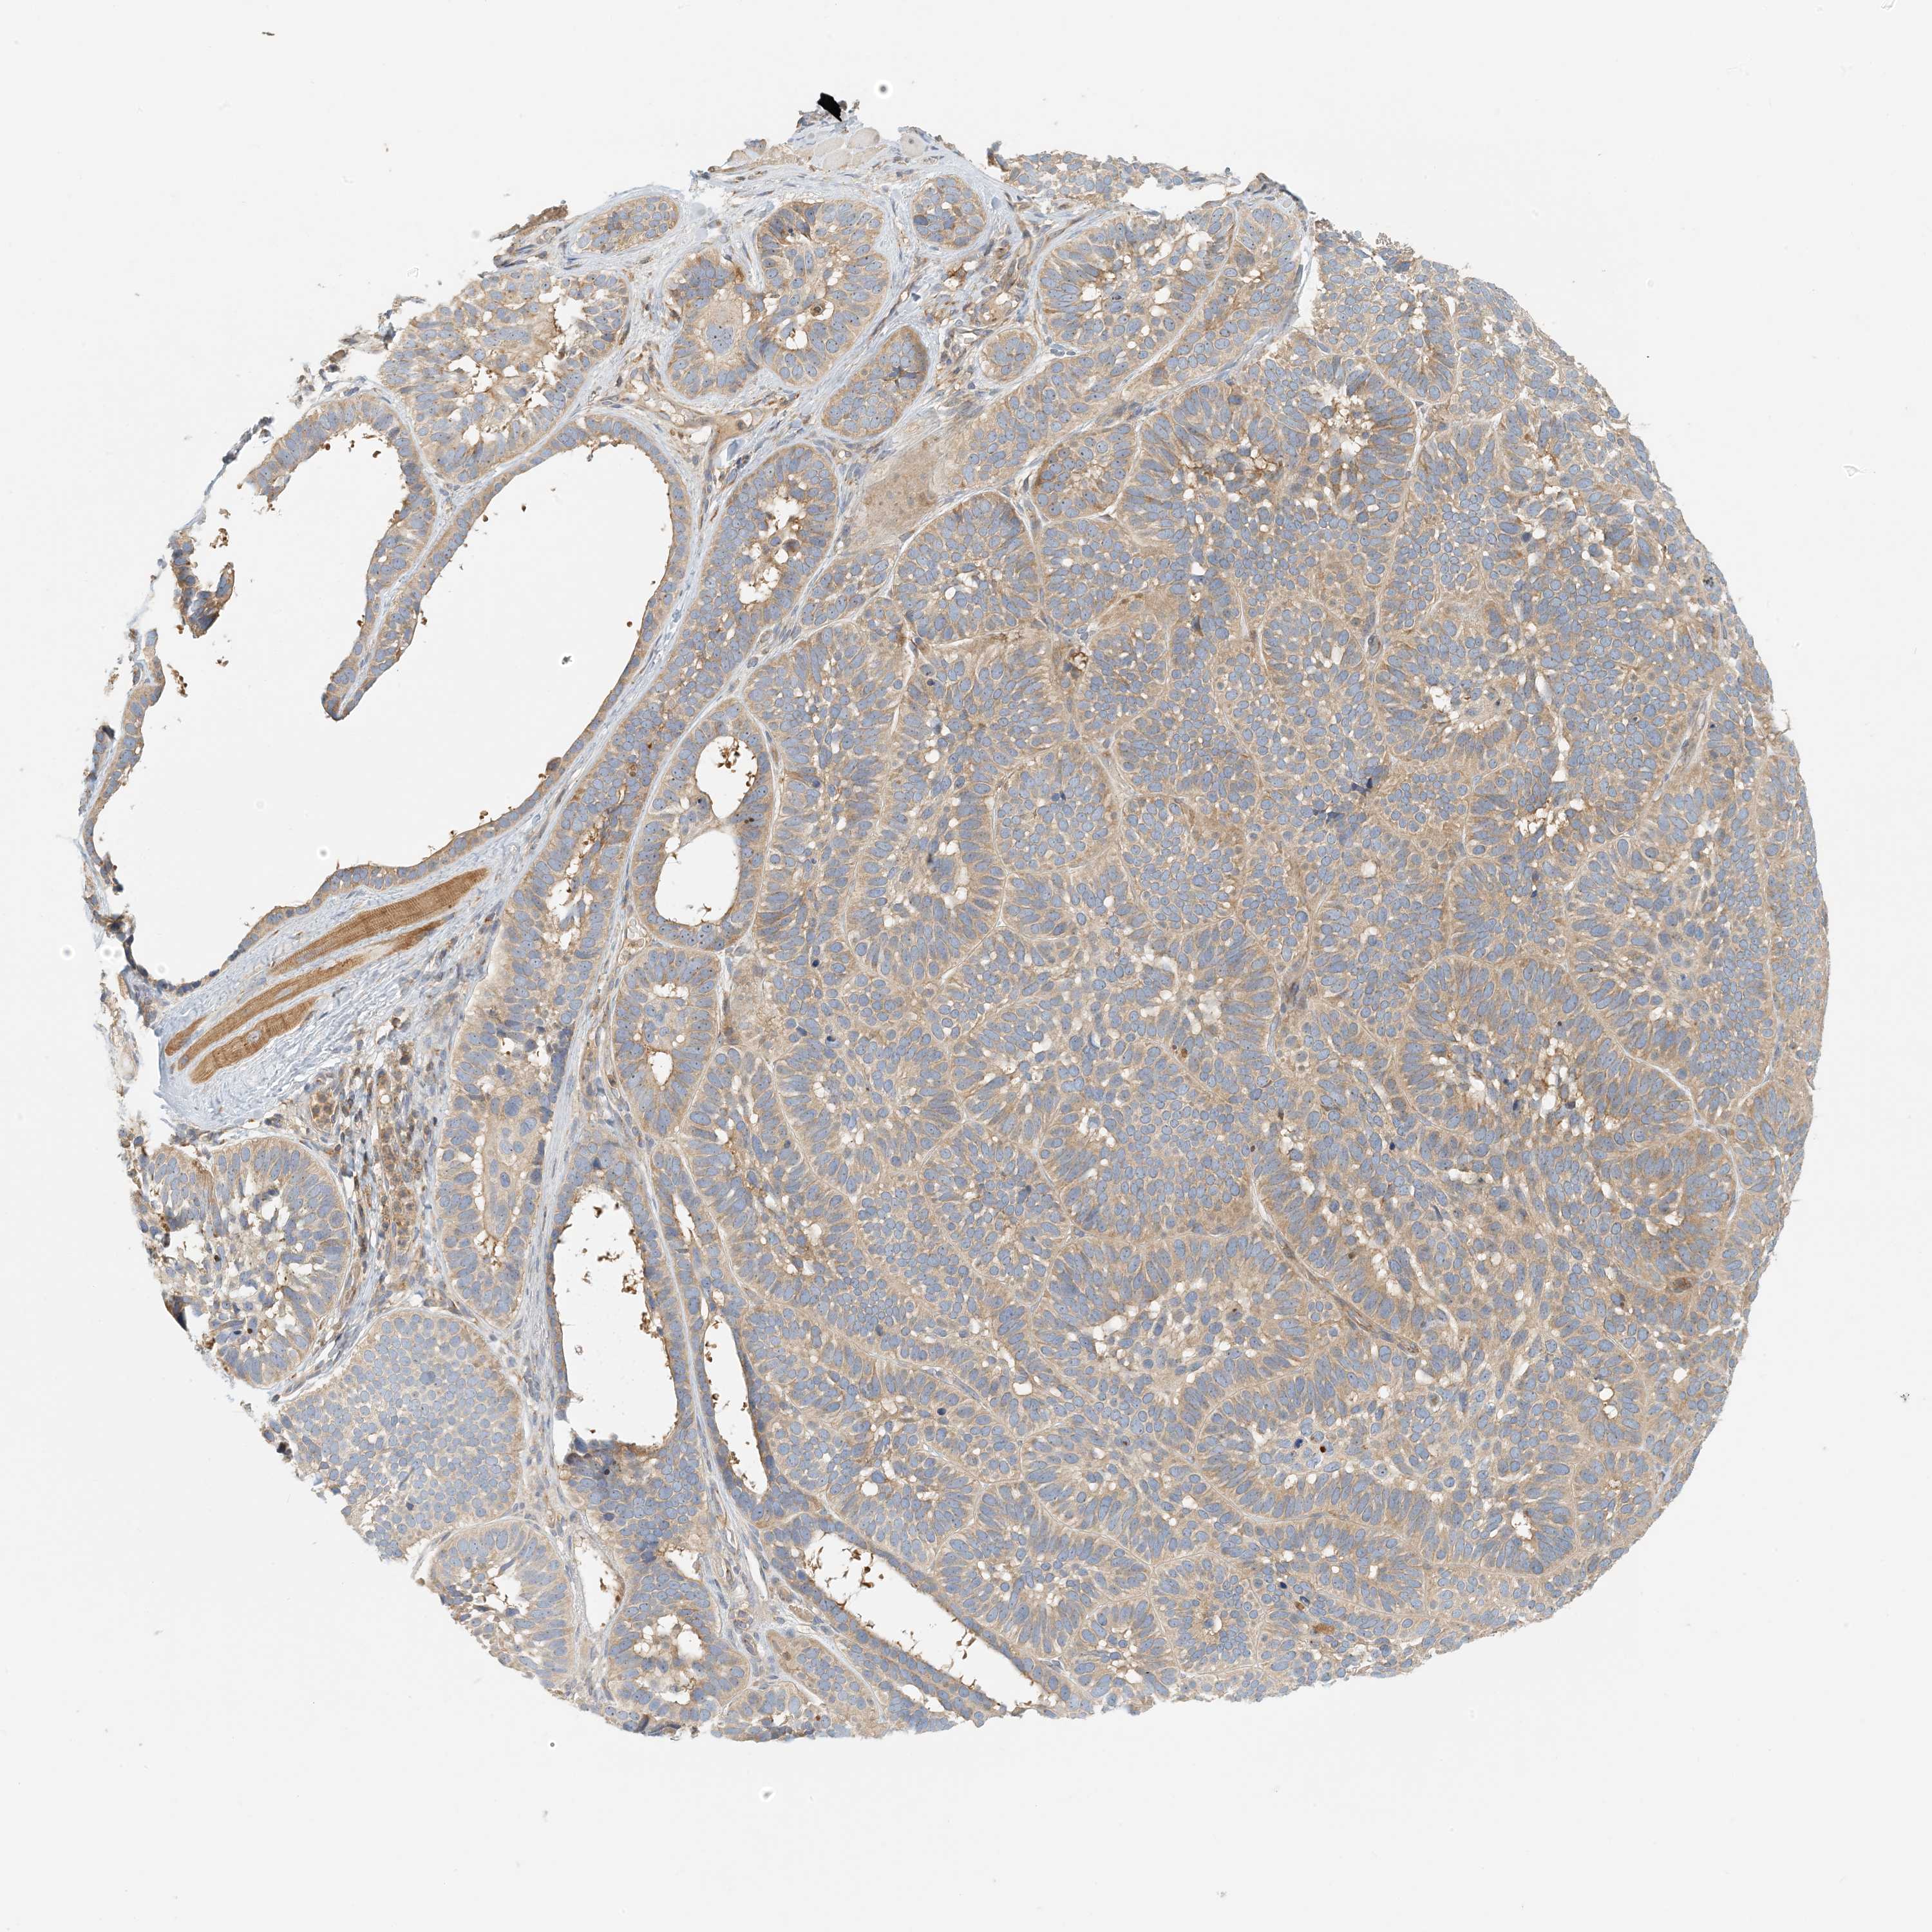

Basal cell and squamous cell cancer

SKIN CANCER - Protein expressioni

A mouse-over function shows sample information and annotation data. Click on an image to view it in a full screen mode. Samples can be filtered based on level of antibody staining by selecting one or several of the following categories: high, medium, low and not detected. The assay and annotation is described here.

Antibody stainingi

Antibody staining in the annotated cell types in the current human tissue is reported as not detected, low, medium, or high, based on conventional immunohistochemistry profiling in selected tissues. This score is based on the combination of the staining intensity and fraction of stained cells.

Each image is clickable and will lead to virtual microscopy that enables deeper exploration of all samples and also displays staining intensity scores, fraction scores and subcellular localization as well as patient and tissue information for each sample.

Antibody HPA035241

Staining

High

Medium

Low

Not detected

Intensity

Strong

Moderate

Weak

Negative

Quantity

>75%

75%-25%

<25%

None

Location

Nuclear

Cytoplasmic/membranous

Cytoplasmic/membranous,nuclear

Squamous cell carcinoma, metastatic, NOS

Squamous cell carcinoma, NOS